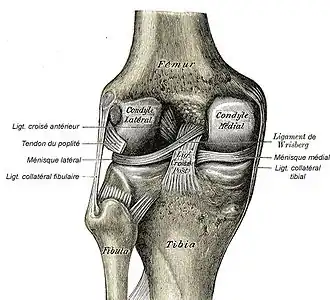

Le ligament collatéral fibulaire (ou ligament latéral externe du genou dans l'ancienne nomenclature) est un ligament de l'articulation fémoro-tibiale.

Le ligament collatéral fibulaire est un long ligament cylindrique situé à distance de la face latérale de la capsule articulaire.

Il prend naissance sur un tubercule de la face latérale du condyle latéral du fémur. Il descend obliquement vers l'arrière en croisant extérieurement le tendon d'origine du muscle poplité. Il se termine sur la face latérale de la tête fibulaire en avant du tendon du muscle biceps fémoral. Celui-ci recouvre la plus grande partie de la face latérale du ligament.

Le ligament collatéral fibulaire s'oppose au genu varum.

C'est un ligament extracapsulaire sans contact ni avec la capsule, ni avec le ménisque.